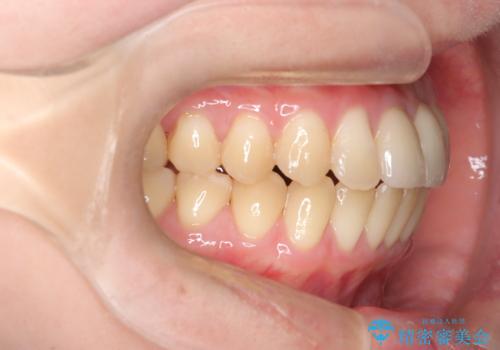

前歯の開咬とシザーズバイトを改善|インビザライン矯正

- 治療計画

前歯が噛まないため咀嚼が困難で、シザーズバイトにより噛み合わせに不調を感じていました。インビザラインを用いて、透明なマウスピースによる目立ちにくい矯正治療を実施。奥歯のシザーズバイトを改善した後、前歯の歯列を緻密に調整し、噛み合わせを整えました。定期的なマウスピース交換を通じて徐々に歯列が改善され、治療終了後には前歯が正常に咬合するようになり、噛み合わせの機能性と審美性が共に向上しました。